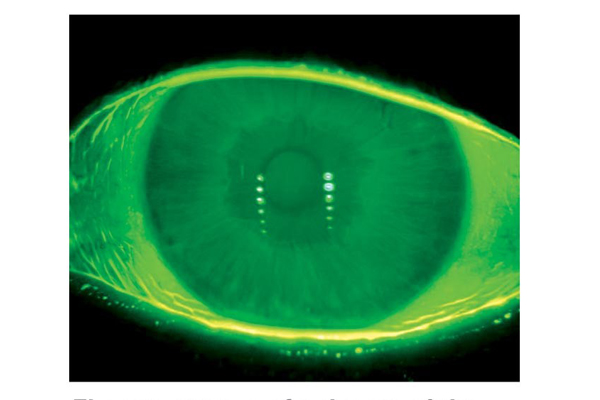

The participating ophthalmologists will get a brief review of anatomical and physiological properties of the ocular surface and tear film. The various diagnostic modalities for imaging the ocular surface and quantifying its structure and function will be discussed and presented. Particular attention will be given to the role of these diagnostic modalities in ocular surface diseases treatment.